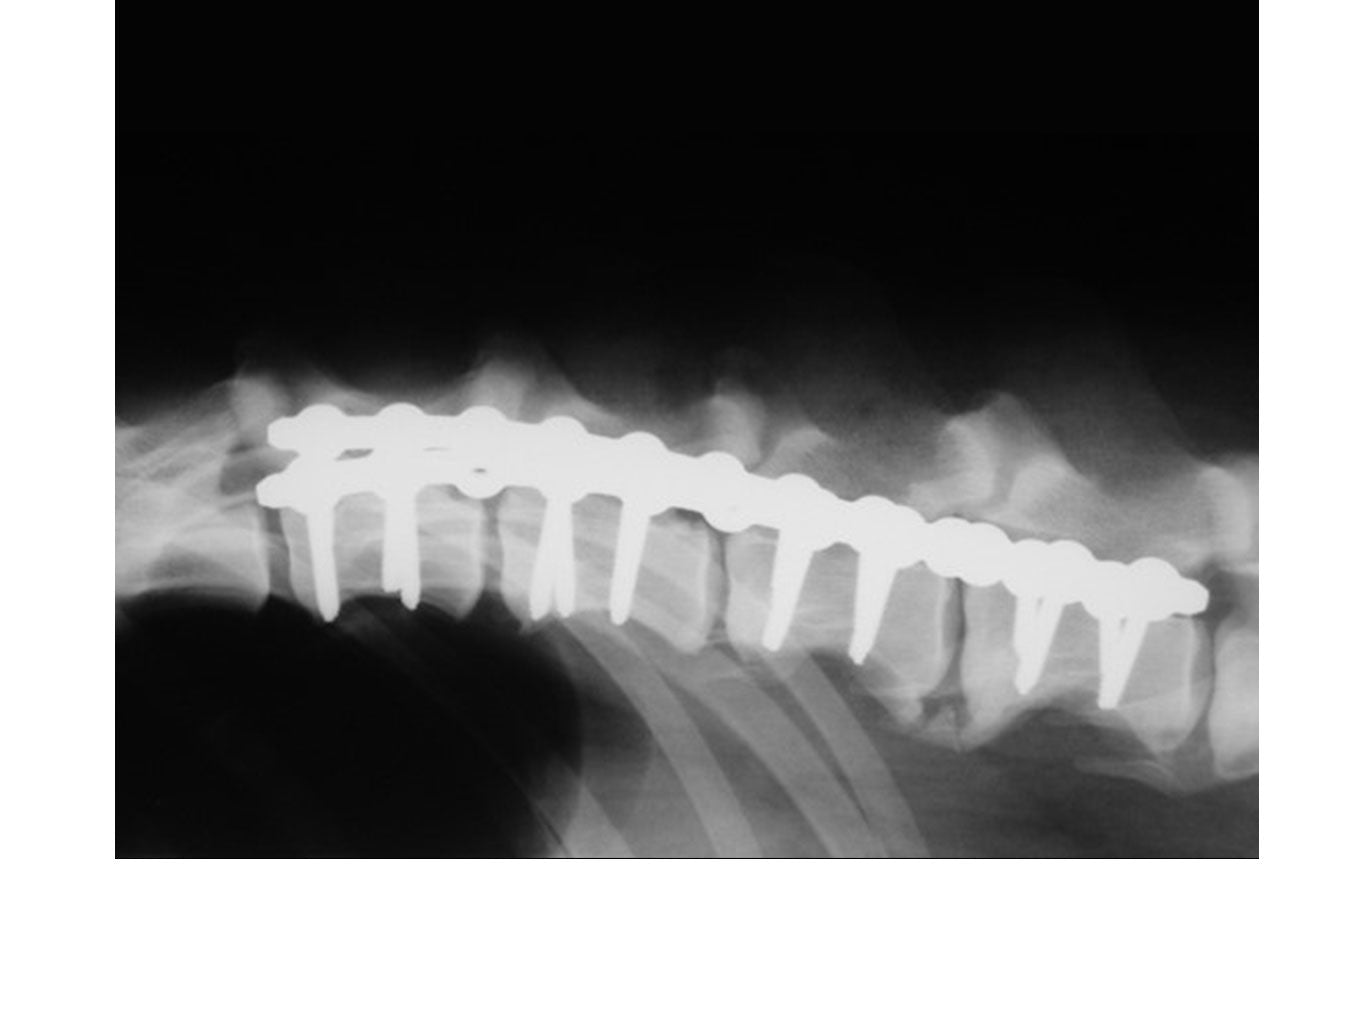

SOP™ uniquely offers a spinal stabilization system with reasonable cost. The SOP™ plates are commonly used in pairs with the screws engaging vertebral pedicles or bodies. The SOP™ can be used similarly to a pedicle screw system for the thoracolumbar spine, or as a locking anterior system for cervical stabilisation/fusions.

// User Cases

Highlighting the cases of these products in real-life situations is vital to demonstrating their success. Below are cases studies of long-term follow up surgeries.